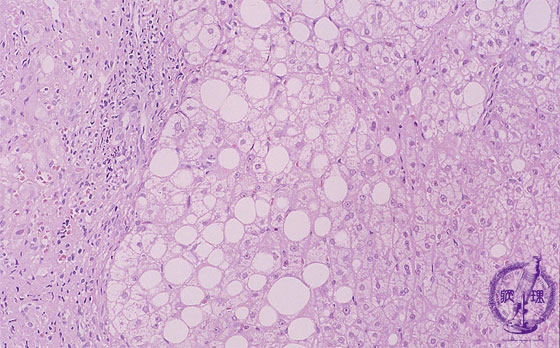

- 10.Liver

- (5)Wilson's disease

Microscopic image (HE stain, intermediate power): Various lesions are observed in the figure. On the left side are infiltrating lymphocytes (yellow circle) and at the center are steatosis and ballooning hepatocytes (red circle). To the right side, there do not appear to be any immediately identifiable abnormalities.

Click the image to see the enlarged image.